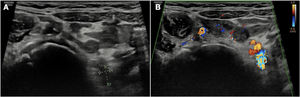

We present the case of a boy aged 15 months with a prenatal diagnosis of pulmonary atresia with intact ventricular septum who underwent pulmonary valve perforation and balloon valvuloplasty with an 8 mm balloon at 9 days post birth (Fig. 1A–D; Appendix B, videos 1–3). At 30 days, due to persistent desaturation, the decision was made to perform percutaneous ductal stenting, since this was less invasive compared to other techniques used to increase pulmonary flow. The procedure, guided by ultrasound, consisted in the delivery, via the left femoral artery and using a 5 F introducer, of a drug-eluting stent (Onyx Frontier, Medtronic, USA) measuring 4.5 × 12 mm to the ductus arteriosus (Fig. 1E and F; Appendix B, videos 4 and 5). Five days after the procedure, the patient experienced vomiting, and the abdominal ultrasound scan used for initial assessment revealed a mass in the left groin, with subsequent Doppler and angio-CT scans allowing visualization of a pseudoaneurysm at the level of the left common iliac artery (Fig. 2A–F).